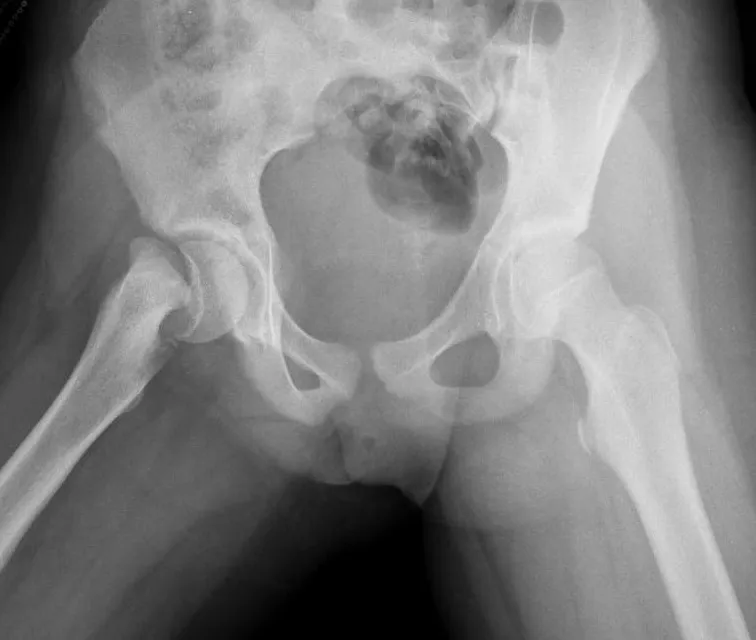

X-ray of a 12-year-old girl who developed sudden pain in her right hip. There is a widening of the physis of the right proximal femur. e Image used on license from Radiopaedia.

<img src="e01d8f22c6a4db1816456f897c12aac7.webp"><br>X-ray of a 12-year-old girl who developed sudden pain in her right hip. There is a widening of the physis of the right proximal femur. e Image used on license from Radiopaedia.